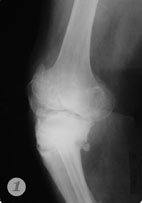

Пример №5 Эндопротезирование коленного сустава

1,2 до операции

3. после операции по эндопротезированию коленного сустава